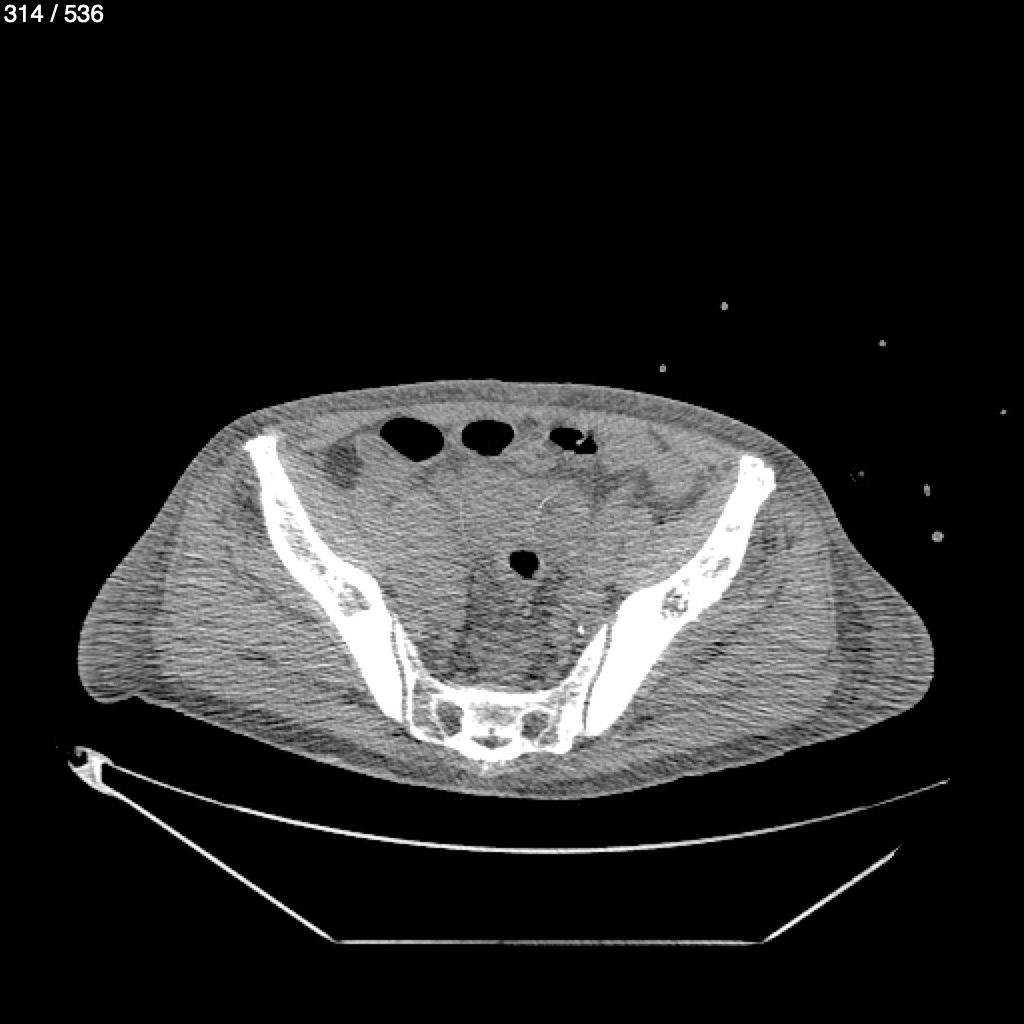

Angel Villalobos Palomeque 73 A - T.C Abdomen Simple